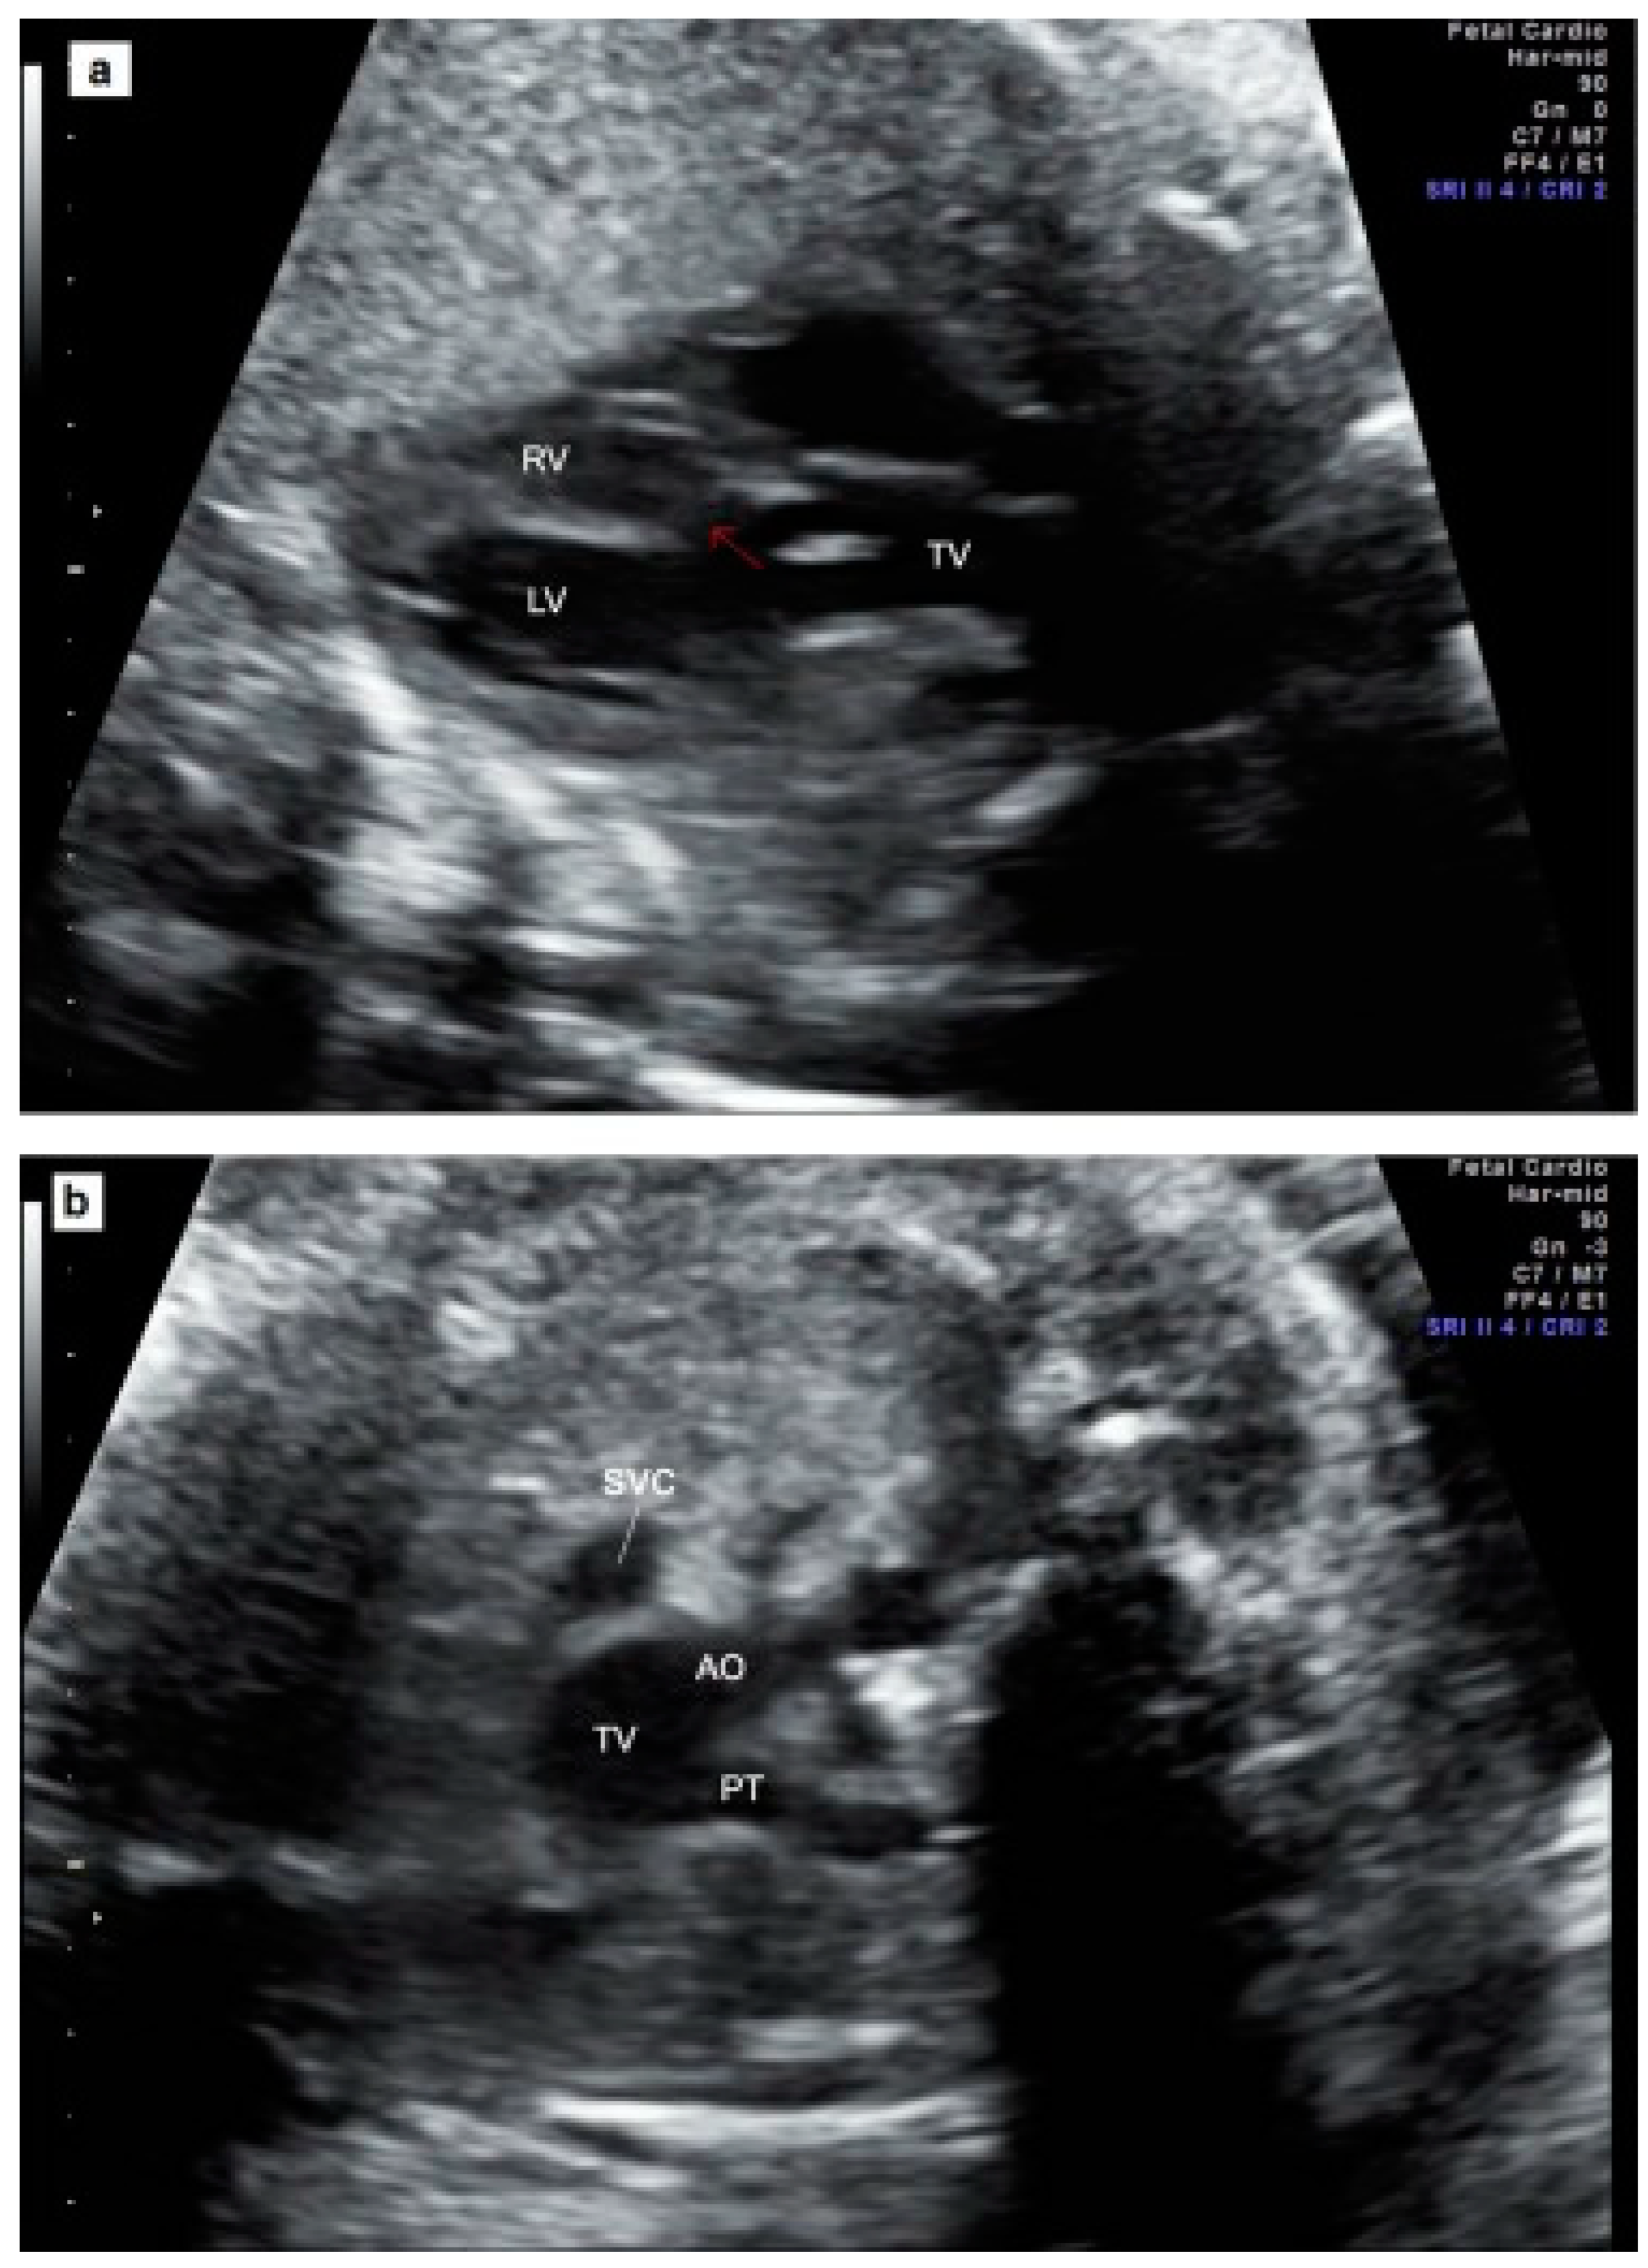

- Mărginean, C.; Gozar, L.; Mărginean, C.O.; Suciu, H.; Togănel, R.; Muntean, I.; Mureşan, M.C. Prenatal diagnosis of the fetal common arterial trunk. A case series. Med. Ultrason. 2018, 20, 100–104. [Google Scholar] [CrossRef]